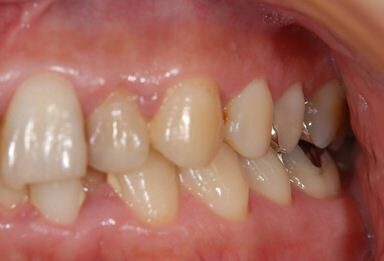

| 性別/年齢 | 男性 / 37歳 | ||||||||||||||||||||||||||||||||

| 主訴 | 数年前に神経を抜く治療をした下顎の歯が、1年ほど前にうずきを感じて治療をした際に、完全に治療するのは難しいと言われた。その歯がぐらつくように感じ始めたので、相談のために来院。 | ||||||||||||||||||||||||||||||||

| 治療内容 | インプラント1本(GBR)、メタルボンドセラミック1本 | ||||||||||||||||||||||||||||||||